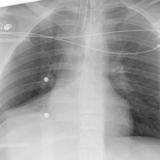

RLL collapse 4 PA

Date: 03/02/2006

Views: 3296